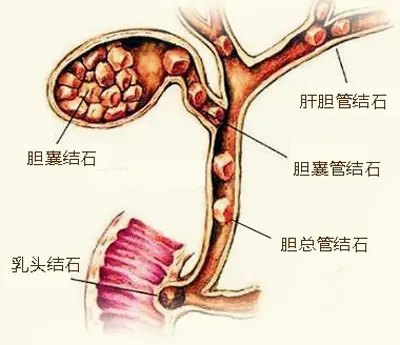

合并胆总管结石或肝内胆管结石

建议:胆囊结石合并肝内、外胆管结石不是CGPC的禁忌,根据患者实际情况选择合适的治疗方案,仍可以保留胆囊。